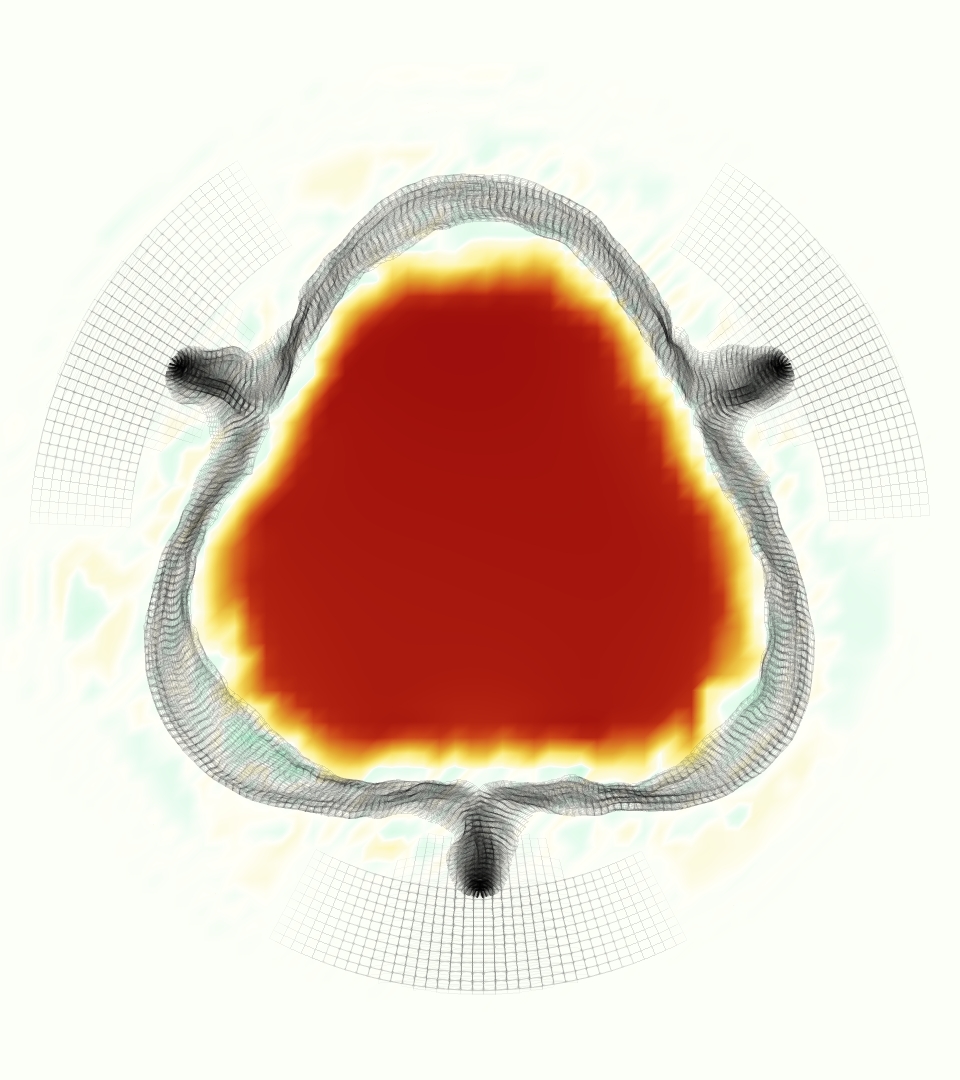

The gross morphology of the model valve that emerged from this process is shown in Figure 4. The free edge was 2.87 cm, corresponding to 3.3 cm in the predicted loaded configuration. After the pinching the leaflets together at the commissures, this left approximately 2.1 cm of free edge rest length per leaflet free to move independently of the other leaflets, within measurement error of ±0.1 cm from the free edge length of 2.2 cm measured on the prostheses. The leaflet rest height was 0.94 cm corresponding to a predicted loaded height of 1.44 cm. The measured leaflet height of 1.3 cm is nearly the predicted loaded height of 1.44 cm, which may be because the leaflets are so compliant in the radial direction, that pulling them flat to measure them achieved substantial stretches. The fiber orientation of the model runs from commissure to commissure and qualitatively matches experimental observations [38], though direct quantitative comparison is beyond the scope of this work. One minor limitation is that we do not add bending rigidity to the leaflets, beyond what emerges from the thickening process described above, and thus may not accurately capture leaflet flutter or other similar behaviors. Based on the thickness of mm, we estimated the mean tangent modulus at the predicted loaded stretches as dynes/cm2 circumferentially and dynes/cm2 radially. The prosthetic valve tissue is fixed in glutaraldehyde, and literature values for the fully-recruited circumferential tangent modulus of fixed porcine aortic valve tissue vary widely. Based on the experimental measurements of Billiar and Sacks and their constitutive law for valves fixed under 4 mmHg of pressure, we evaluated their constitutive law at the relevant stretches and and estimated the circumferential tangent modulus to be dynes/cm2 [6]. Rousseau et al. reported moduli ranging from to dynes/cm2, depending on the applied preload during fixation [36]. Sung et al. reported moduli ranging from to dynes/cm2, depending on fixation pressure [43]. Thus our estimated tangent modulus falls within the range of existing studies, so we considered our resultant modulus in good agreement given the complexity of the steps involved, phenomenological nature of the constitutive law and uncertainties in experiments. We do not have access to the precise material properties of the prosthetic valve, and further, the only literature we could find on the material properties of a similar prostheses reported the tangent modulus at one particular loading, which did not appear to be at a relevant stretch for comparisons with our model [19]. Thus, our model has material properties in a reasonable range for a fixed aortic valve prostheses (placed in the pulmonary position in our simulations), but it does not directly model the material properties of the prostheses.

We constructed the model vessel for FSI simulations from data from the MRI scans (Figure 4). The signal magnitude of 3D printed model material is distinct from the signal of the fluid in the scans, and we applied a thresholding operation to generate a three-dimensional model of the printed vessel surface. Using the MRI data ensured that the MRI and simulation coordinates were consistent in space and there were no alignment or registration errors. While using the files that generated the 3D printed model would have offered more spatial fidelity, the potential error in flow fields due to any mis-registration would have likely been much more substantial. Using Meshmixer (San Rafael, CA), we smoothed the mesh to remove stair-step effects and removed artifacts from the valve scaffold. We then remeshed to the desired edge length of 0.25 mm and extruded the model 0.25 mm and 0.5 mm to create a three-layer structure. As in the valve, this serves to eliminate the “grid aligned artifact” that can occur with pressure differences across thin membranes in the IB method [16]. Flow extenders of length 1 cm were added to the vessel at the inlet and both outlets to ensure that the normal to the vessel was aligned with the normal of the fluid box at the inlets and outlets. In FSI simulations, the vessel was held in place using target points, stiff springs of zero rest length that connect the current position of each model node to its desired position (Section 3.3). Additional linear springs are placed on each edge in the triangulated model. These springs are not meant to model a particular material and only serve to keep the vessel rigid and stationary throughout the simulation.

At = 0, the axial slice directly at the valve annulus shown in columns 1 and 2 in Figure 6, there was excellent agreement between the simulation and experiment over the cardiac cycle in the speed and shape of the jet through the valve. In both cases, the axial velocity increased as the flow accelerated during systole and the valve leaflets opened, then decreased during diastole with slight negative velocity before the valve leaflets were fully closed. The forward flow through the valve annulus did not form a full circle, but rather developed a triangular shape with a point of the triangle forming along the interior curve of the vessel, at the bottom of the axial slices. At = 0, the points of this triangular jet shape aligned with the commissures of the valve. This shape persisted during peak systole and was well-matched by the simulation.

The axial slice = 0.625 cm, shown in columns 3 and 4 in Figure 6, cut through the support scaffolding of the valve and the leaflets when they are open. In the experimental data, the shape of the jet changed as it moved downstream. A triangular shape occurred, but the points were then aligned with the middle of each open leaflet as opposed to the commissures. Those points were also more rounded than they were at = 0. The peak velocity of the jet was faster at = 0.625 cm than at = 0, as the flow accelerated through the open valve leaflets. The simulation produced these features at = 0.625 cm. The triangular shape of the jet shifted similarly, and its speed increased compared to the upstream slice. As the flow decelerated into diastole, the jet shape remained roughly triangular but diminished in intensity before disappearing after valve closure.

The jet continued to develop at = 1.25 cm, an axial slice immediately downstream of the valve scaffolding and open leaflets, shown in columns 5 and 6 in Figure 6. In the experimental data, the points of the triangular jet shape extended further towards the vessel wall. In addition, regions of reversed flow developed in the locations downstream of the commissures, resulting in curved sides to the shape of the jet. Each tip of the jet was unique, due to variations in the individual leaflets in the physical bioprosthetic valve. These variations are apparent in the velocity fields, possibly because the jet edges are similar enough cycle to cycle that irregularities are still being captured even with phase averaging. Further discussion of these features can be found in Schiavone et al. [39], which showed that the jet tip shapes occurred in different pulmonary anatomies, demonstrating that they were likely due to inherent properties of each leaflet. The leaflets in the mathematical model of the valve are identical, so these nuances in leaflet variation could not be replicated. The simulation did capture some of the extension of the tips of the jet, as they were closer to vessel wall at slice = 1.25 cm than = 0.625 cm. The curves in the triangular sides of the jet were also present in the simulation, though they were less pronounced than the experimental data. At both = 0.625 cm and = 1.25 cm, the jet shape in the simulation was smoother than the jet in experiment. It is possible that the free edges of the leaflets in the mathematical model are not fully replicating the behavior of the physical leaflets of the bioprosthetic valve, in particular the amplitude or frequency of leaflet flutter, leading to the variations seen in the jet shape at = 1.25 cm downstream of the leaflet edges. The simulation, however, does capture the key features of the triangular shape and speed of the jet. Overall, qualitative comparisons demonstrated that the simulation reproduced key features of the flow during systole and diastole.

The phase-averaged, resampled velocity fields during peak systole and flow rates at each resolution are shown in Figure 10. Despite the limitations discussed above, we observe similar qualitative trends in the flow field at all resolutions. At all resolutions, a jet formed and angled up downstream of the valve orifice, as shown in the sagittal view. The jets showed a triangle-like cross section at with points aligned with the commissures. At cm, the jet appears like a rounded triangle in the opposing orientation, with its points aligned with the center of the leaflets. At cm, the jet is narrower downstream of the commissures, and wider downstream of the leaflets, again with a triangle-like cross section. The area of the jet increased with resolution, as expected given the IB method thickening of the valve structure. The narrowed jets at the two more coarse resolutions show locally elevated velocities relative to the two more fine resolutions. Figure 11 shows the instantaneous velocity fields at each resolution in the same axial and sagittal views. At 0.9 mm, the sagittal view shows a qualitatively different jet than at finer resolutions, with regions of lower velocity farther from the vessel wall, indicating insufficient resolution. At 0.9 and 0.68 mm, the jet is visibly narrowed compared to higher resolutions. While some features are similar at these two coarse resolutions, we conclude that the narrower jets indicate these simulations are under-resolved. Flows in the three finest resolutions, 0.45, 0.34 and 0.28 mm. appeared qualitatively similar, with slightly more fine structure detail in both the axial and sagittal views present at the edges of the jet. The jets in the axial views all showed a similar triangle-like cross section, slightly narrower downstream of the commissures, as in the phase-averaged fields. In both the phase-averaged and instantaneous fields, the three finest resolutions appear sufficiently similar that the conclusions of this study would be identical with any of these resolutions.